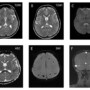

•Axial T2 images (A,B) show hyperintensity in posterior limbs of internal capsules and splenium of corpus callosum with diffusion restriction in splenium (C,D) • •Axial SWI (E) shows few microhemorrhages in both frontal and parietal white matter. •3D TOF venogram (E) shows normal superior sagittal and transverse sinuses. TOF angiogram was unremarkable.

Bilateral symmetrical T2 and FLAIR hyperintensities involving corpus callosum (especially splenium), corona radiata, internal capsules and cerebral peduncles. These signal changes appear bright on DWI in initial phase.

The “wine glass” appearance on coronal T2 image in classical cases due to involvement of corticospinal tracts.